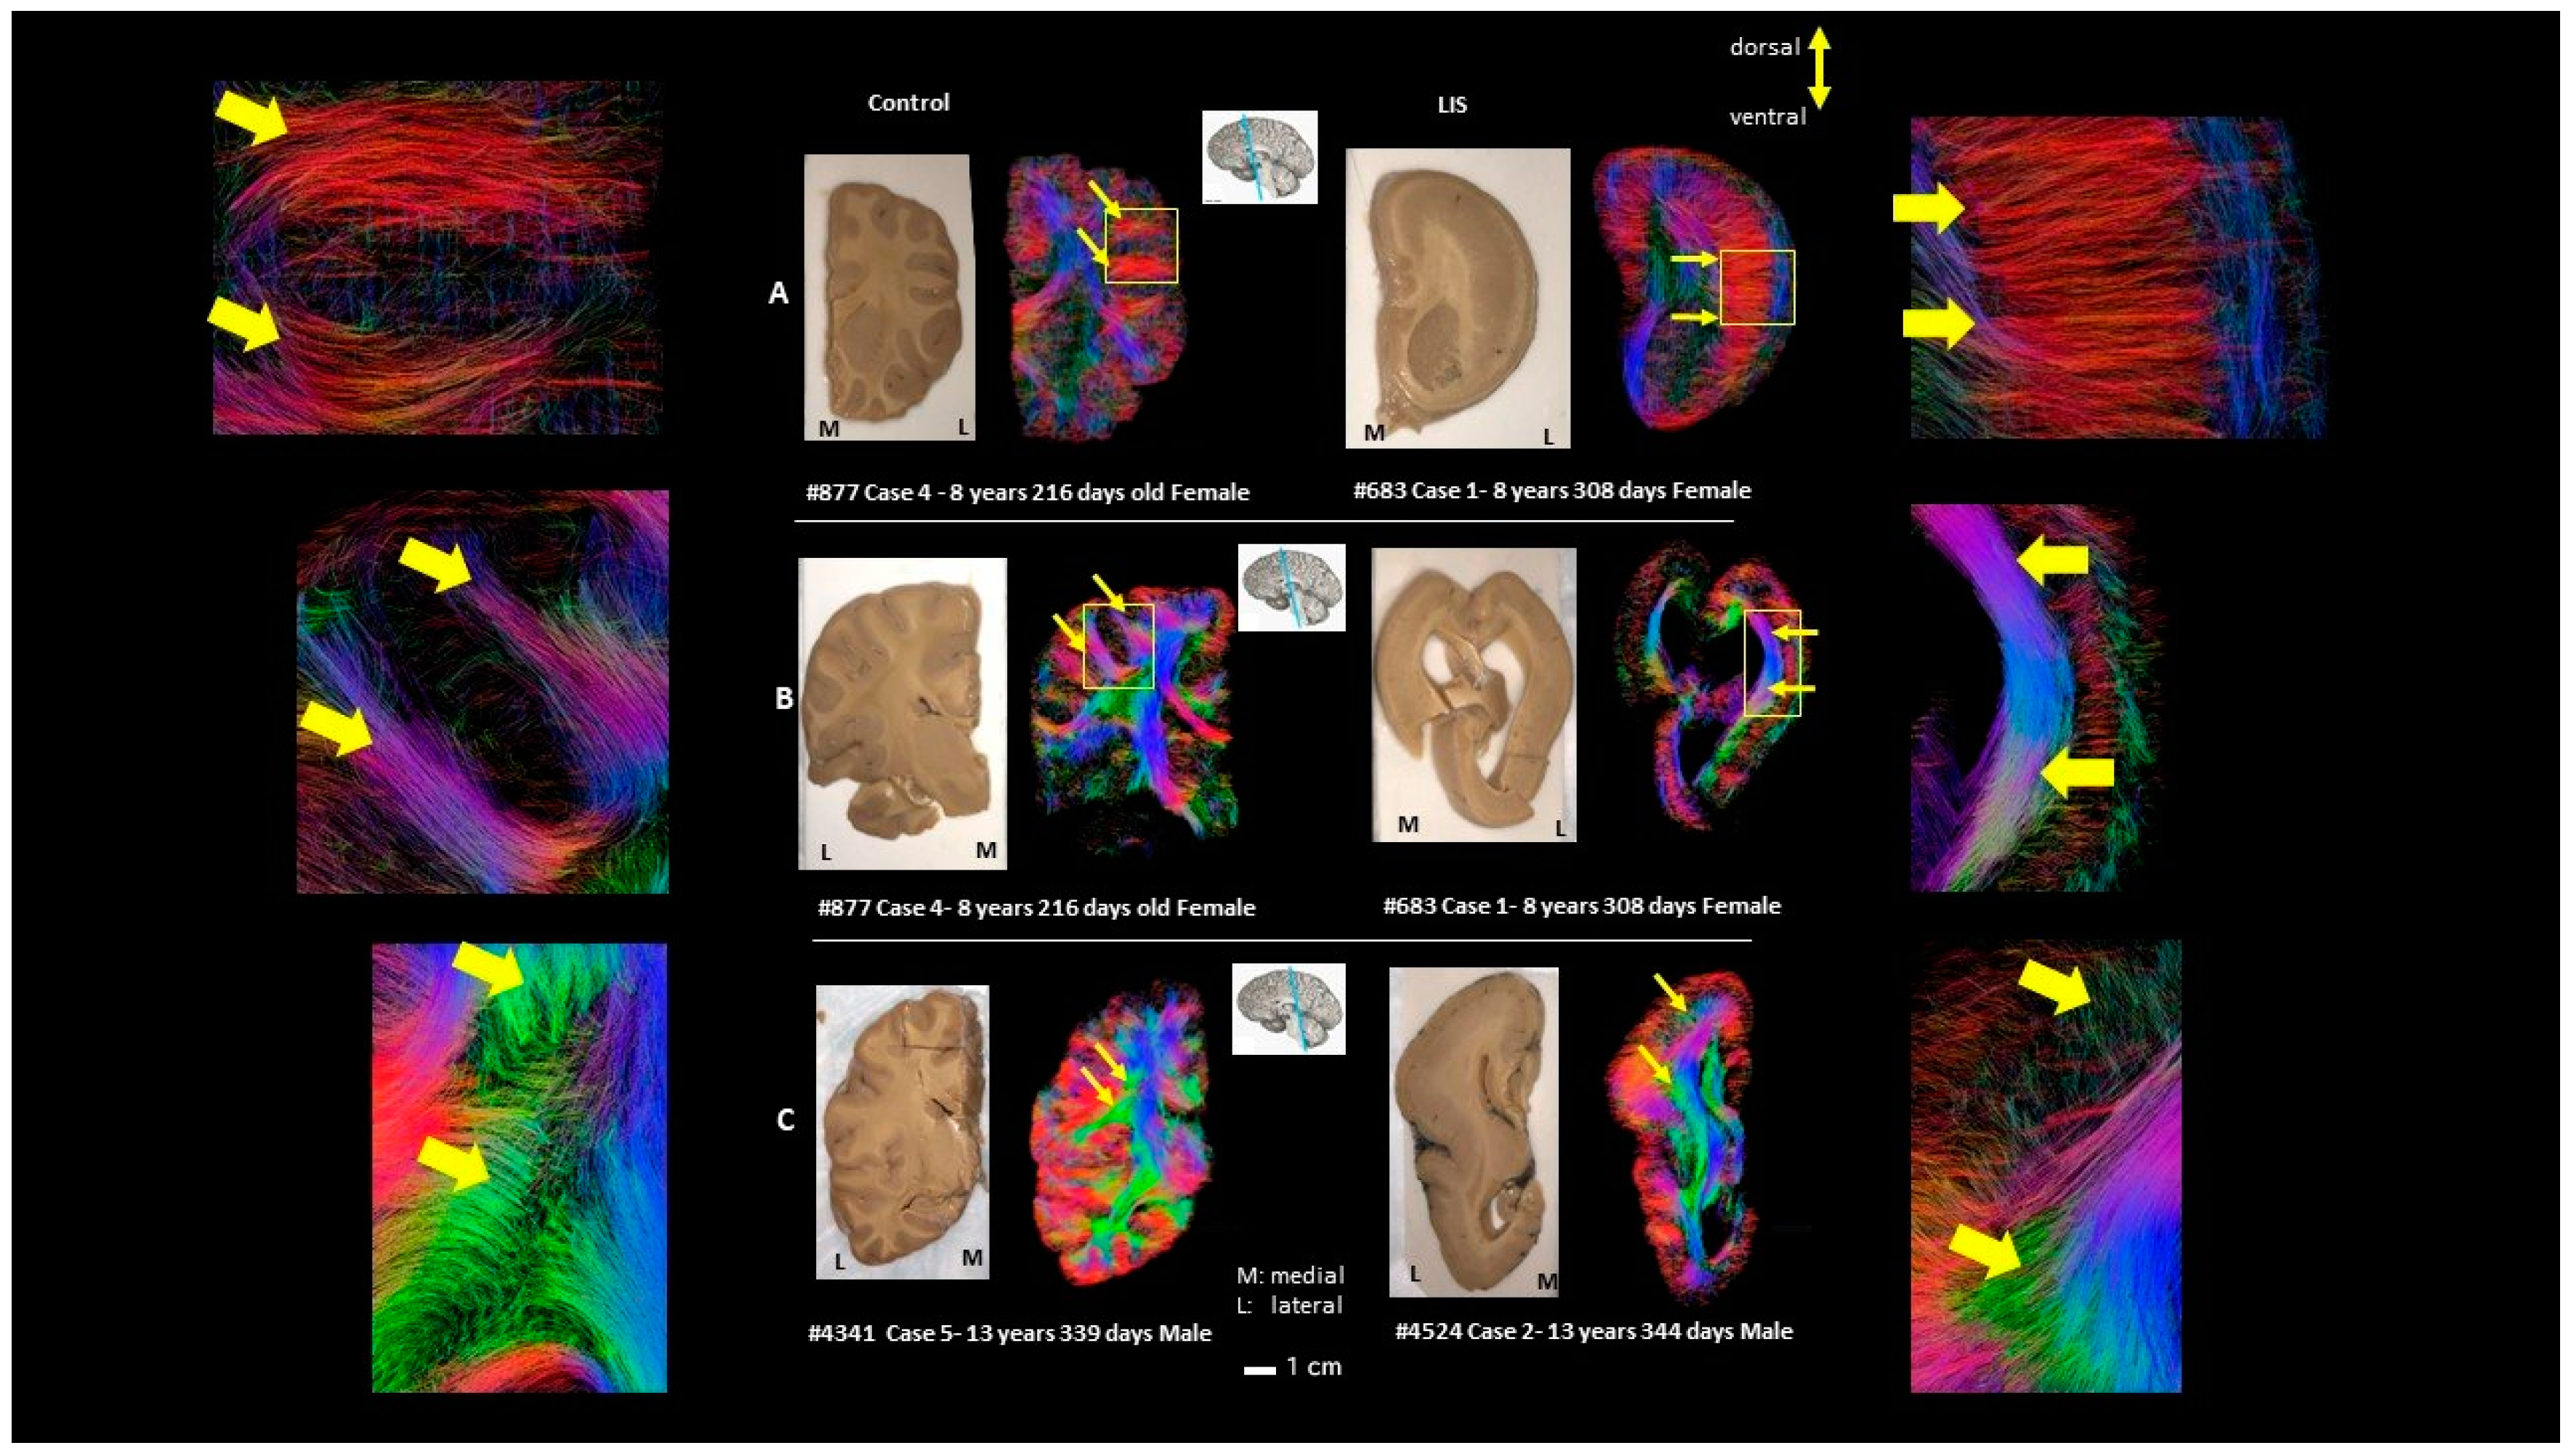

3. Results

4. Discussion

4.1. Developmental Aspect of the LIS Brains

4.2. Microanatomy of Lissencephaly